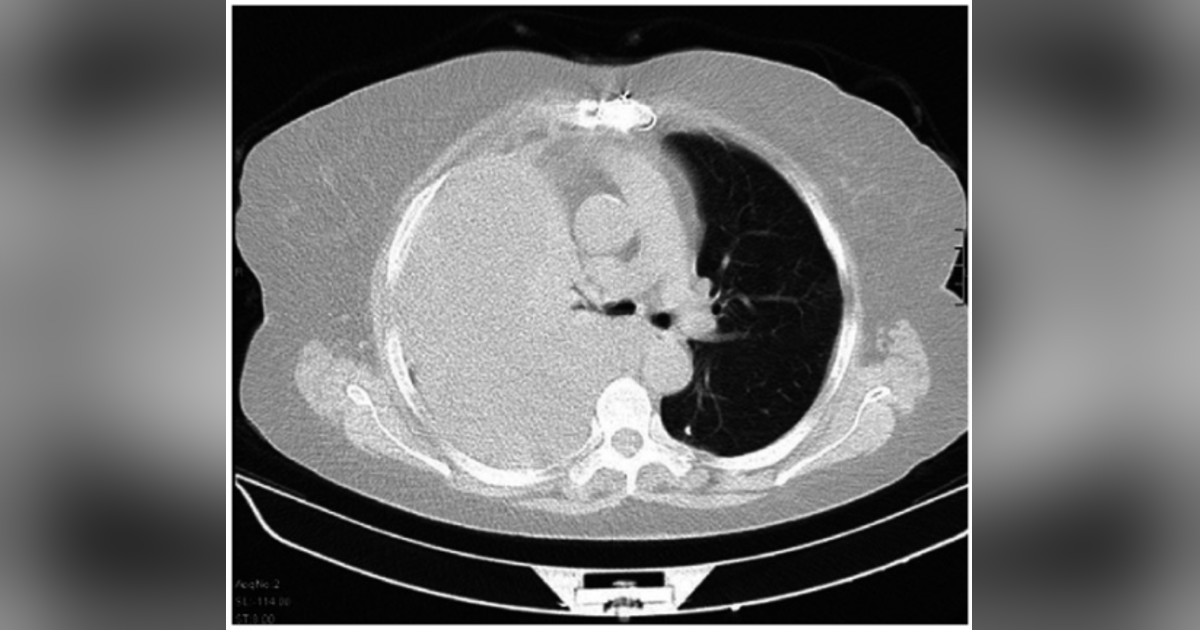

In this episode of Journal Club, Dr. Hassaballa discusses the recent study comparing small-bore to large-bore chest tubes for hemothorax drainage.